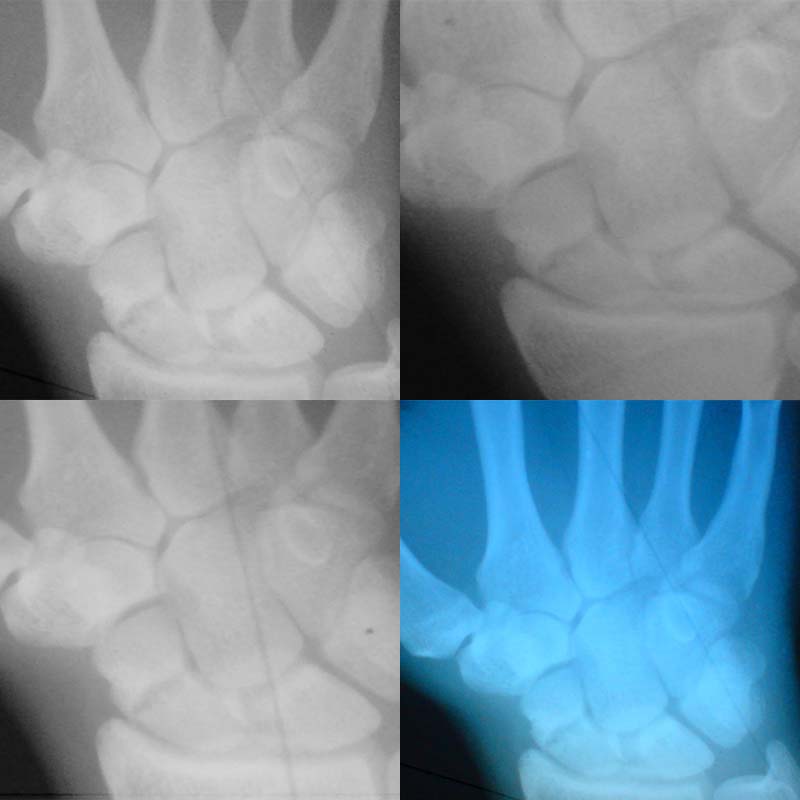

День добрый.Ситуация такова, 2 месяца назад (11 ноября) я получил травму правой руки, упал.Обратился к травматологу - сделали снимок сказали кости целы это ушиб. Боль не проходила, хоть и терпима. 13 января я опять пошел в больницу сделал снимок, диагноз - перелом ладьевидной кости. Врач направил в областную больницу так как думал что у меня там уже киста. Там сделали снимок обеих рук сказали что это не киста, а неправильно сростается кость и нужна операция. И я не знаю делать операцию или нет.

• Кликните для загрузки файла Untitled-1.jpg

Если сохраняется болевой на сегоднящний день -- необходимо оперативное лечение.

Надо оперировать. Если есть в пределах досягаемости отделение хирургии кисти - это лучший вариант.